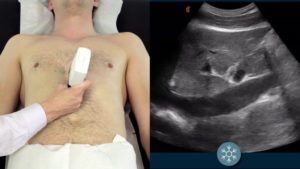

*Using a the Clarius linear-array transducer, Dr. Thomas Cook was able to get a get a good image of the eye in a patient with acute vision loss. As indicated by Dr Cook, there is no evidence of retinal detachment, vitreous hemorrhage, or papilledema.